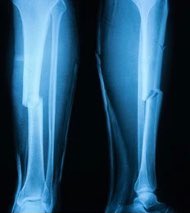

🔹 الأشعة السينية (X-ray) صورتين

🔹 في بعض الحالات قد تحتاج إلى أشعة مقطعية (CT) مثل الكسر الإجهادي، وكسور داخل المفصل

◻️ التشريح

تتكون الساق من عظمة الظنبوب (Tibia) في الجانب الأقرب للوسط، والشظية (Fibula) على الجانب الخارجي، ترتبط العظمتين بالغشاء بين العظمي (Interosseous membrane) في الساق مشكلًا نوع من المفاصل الليفية يدعى التلازم (Syndesmosis) ذات الحركة القليلة جدًا.

وتشارك عظمة الساق الظنبوب في مفصل الركبة من الأعلى ومفصل الكاحل من الأسفل، أما الشظية لا تشارك في مفصل الركبة.